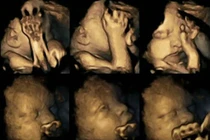

| Hình ảnh thai nhi trên và dưới hoàn toàn khác nhau. |

| Các nhà nghiên cứu đã dùng siêu âm 4D để thấy rõ tình trạng em bé trong bụng mẹ. |

Phụ nữ mang thai đã được kêu gọi từ bỏ thuốc lá vì những nguy cơ như sinh non, các vấn đề về hô hấp và thậm chí là tử vong. Thậm chí, thai nhi có mẹ hút thuốc có thể bị trì hoãn hệ thống phát triển của thần kinh trung ương. Nghiên cứu này được tiến hành bởi đại học Durham và Lancaster, được công bố trên tạp chí Acta Paediatrica.